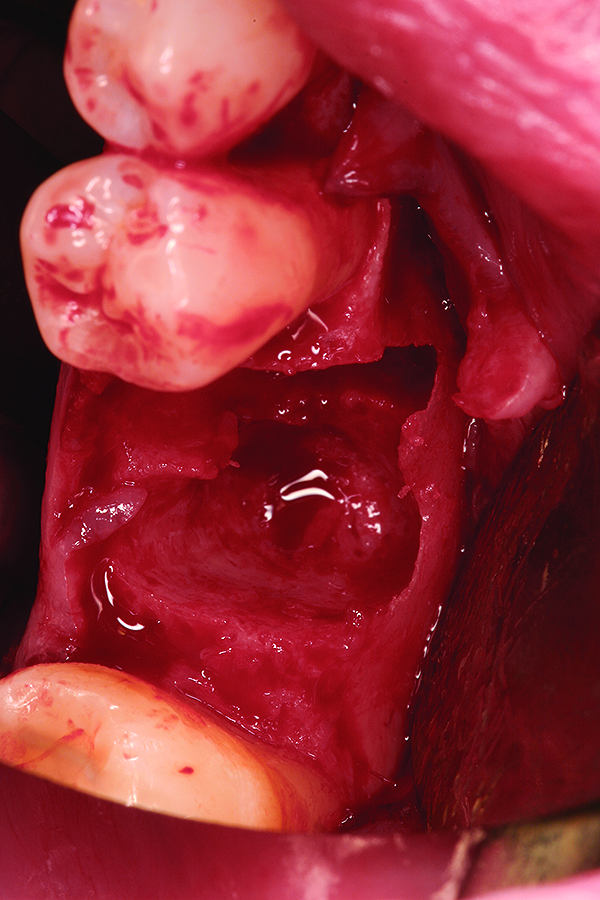

Fig 9. Note the significant osseous defect in the buccal osseous wall following atraumatic tooth extraction.

Figure 9

Fig 16. Note the significant dehiscence defect in the buccal wall prior to tooth extraction.

Figure 16